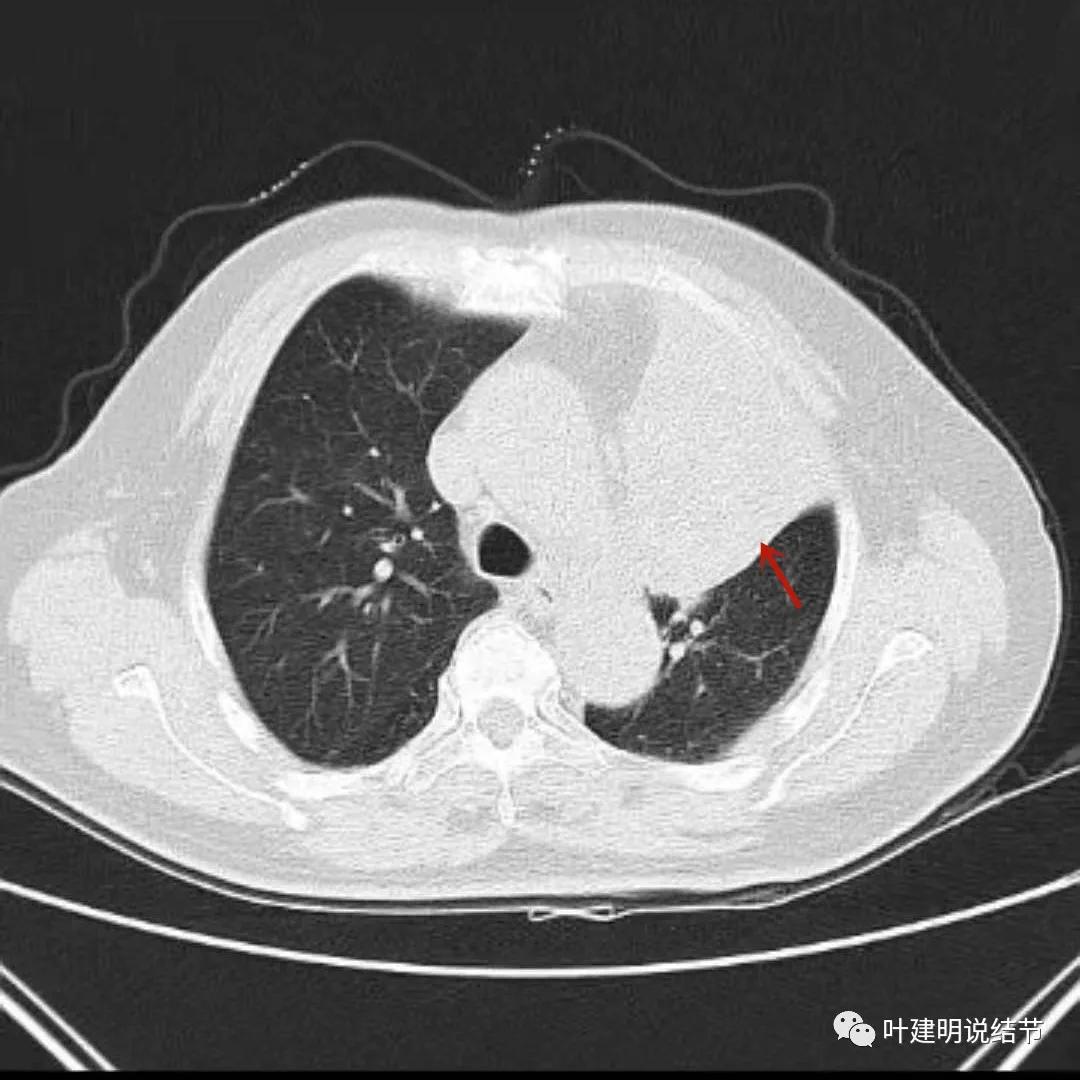

上图红色箭头示肿瘤,绿色箭头示肺不张

上图肺窗见左上叶实性密度影